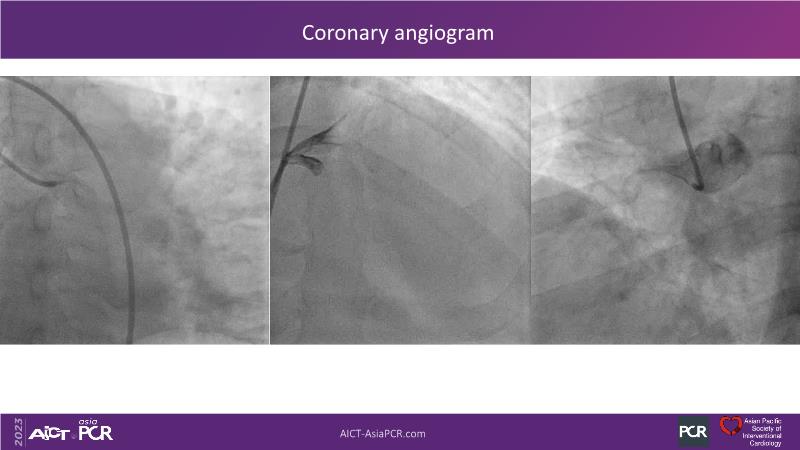

Leave nothing behind: DCB-only PCI strategy - How DCB evidence has changed today's practice?

This session offers an opportunity to stay informed about the recent developments in the International DCB Consensus Group, gain insights into the latest clinical data and real-world experiences related to drug-coated balloon (DCB)-only PCI, understand the safety aspects of DCB in managing complex PCI cases, and participate in an interactive discussion with experts.